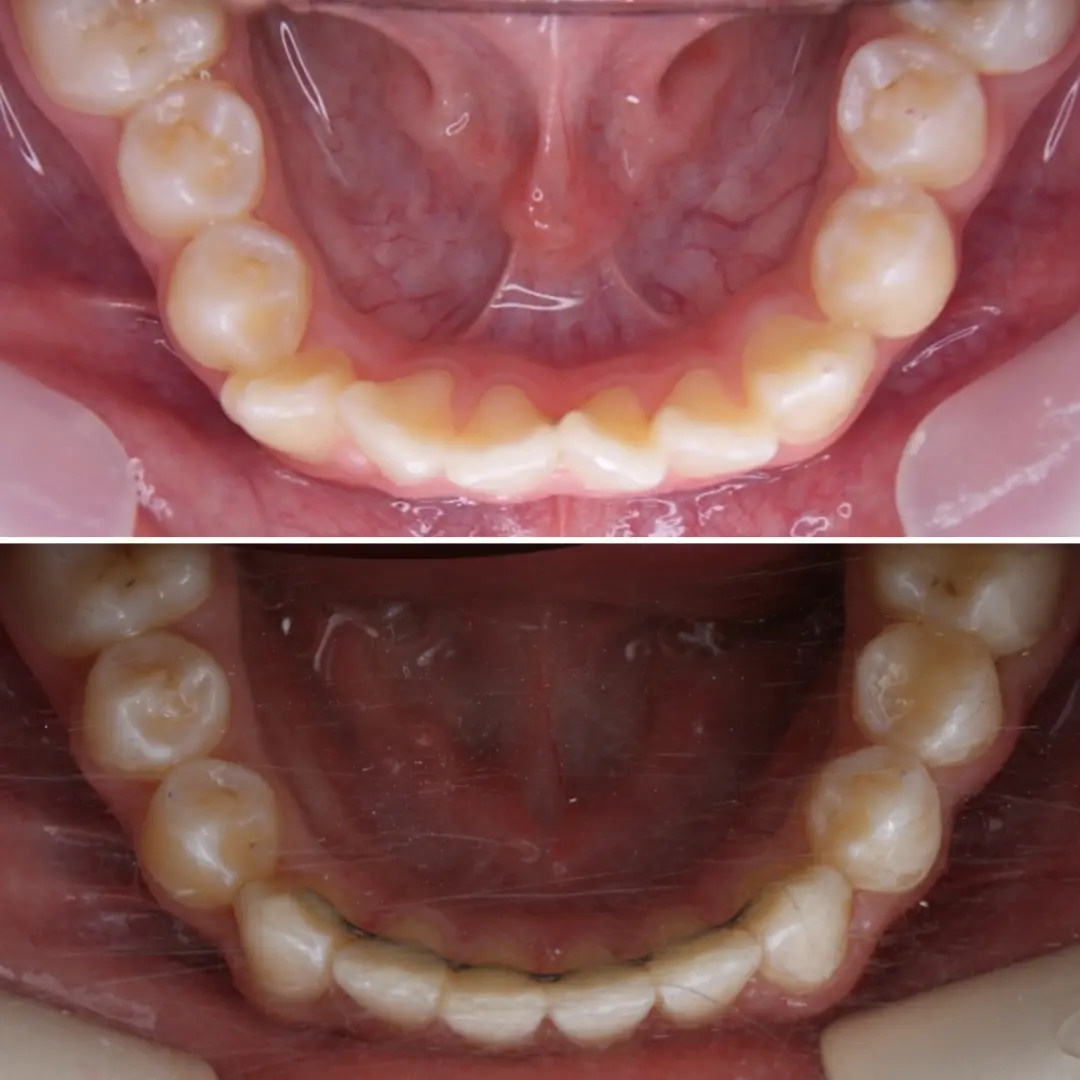

🔷️ Промежуточный результат лечения на аппарате Марко Роса (6 месяцев). Пациенту 7 лет. Самое удивительное - как "отвечает" на лечение нижняя челюсть: расширяется, меняется её положение и корректируется дистальный прикус, выравниваются нижние зубы, хотя никаких аппаратов на нижней челюсти не было!

❓Почему на нижней челюсти зубы тоже прорезываются неровно?

▶️ При сужении верхней челюсти сужается и нижняя, так как нижняя под верхнюю "подстраивается". Верхняя челюсть словно зажимает в тиски нижнюю челюсть и тормозит её рост.

❓Нижнюю челюсть тоже нужно расширять?

▶️ При достаточном расширении верхней челюсти, нижняя начинает "расти" и "подстраиваться" под верхнюю сама. Такая адаптация может занять год. Но часто мы помогаем расширению нижней челюсти (дополнительные аппараты, гимнастика для мышц лица и рта, др.)